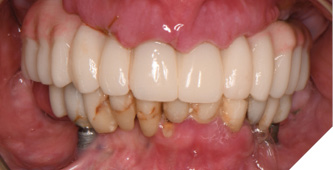

The patient returned 2 months later (due to patient scheduling delays) and the maxillary and mandibular Nexus restorations were inserted (Figs. 26A-C). Passive seating of the restorations were confirmed with the Sheffield test and radiographic confirmation. The occlusion was checked and final radiographs taken (Fig. 27).

Fig. 26A

Fig. 26B

Fig. 26C

Fig. 27